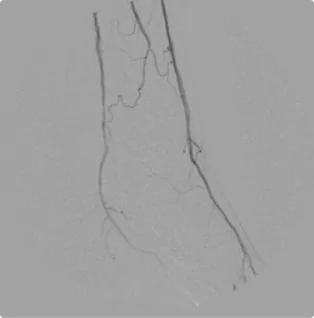

Male – Age 86

Referred by his Podiatrist for his Varicose Veins and Pre-Podiatric Surgical Evaluation

Although this patient was first referred for suspected venous disease, his first ultrasound revealed critical arterial disease in the left calf that placed him at high risk for amputation. The tibial arteries- the branches of arteries that deliver blood to the front and back of the calf- were completely shut off, starving the lower leg of blood and causing severe pain. He was scheduled for intervention the next week. After treating the arteries down the leg and into the foot with atherectomy, angioplasty, and stent placement, Dr. Goldstein restored flow through all three arterial branches and down into the foot. Proper circulation was restored, and the foot was salvaged. Since the first treatment, Dr. Goldstein has closely monitored flow through the arteries to maintain a healthy flow.

Before

Arterial flow through the calf after the intervention. All three arterial branches are present and flowing smoothly, delivering proper flow to the calf and down into the foot to eliminate the need for amputation.